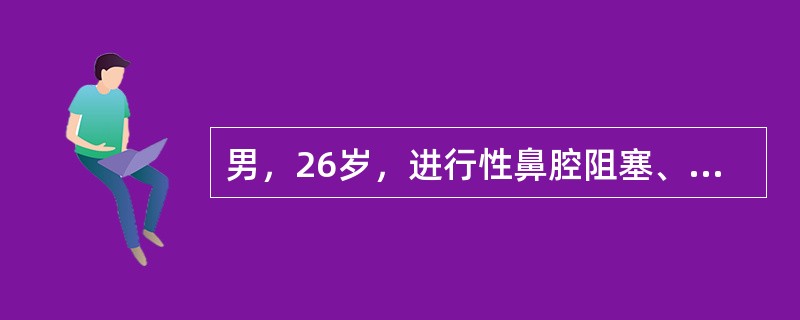

男,26岁,进行性鼻腔阻塞、流涕来院就诊,近两年持续性头痛、头晕,筛窦区病变影像检查如图,最可能的诊断是

A.脊索瘤伴左上颌窦炎

B.软骨瘤伴左上颌窦炎

C.骨化性纤维瘤伴左上颌窦炎

D.骨结核伴左上颌窦炎

E.骨纤维异常增殖症伴左上颌窦炎

男,26岁,进行性鼻腔阻塞、流涕来院就诊,近两年持续性头痛、头晕,筛窦区病变影像检查如图,最可能的诊断是<img border="0" style="width:

[单选题]男,26岁,进行性鼻腔阻塞、流涕来院就诊,近两年持续性头痛、头晕,筛窦区病变影像检查如图,最可能的诊断是A.脊索瘤伴左上颌窦炎B.软骨瘤伴左上颌窦炎C

男,26岁,进行性鼻腔阻塞、流涕来院就诊,近两年持续性头痛、头晕,筛窦区病变影像检查如图,最可能的诊断是()<img border="0" style="width

[单选题]男,26岁,进行性鼻腔阻塞、流涕来院就诊,近两年持续性头痛、头晕,筛窦区病变影像检查如图,最可能的诊断是()A.脊索瘤伴左上颌窦炎B.软骨瘤伴左上颌窦

男,26岁,进行性鼻腔阻塞、流涕来院就诊,近两年持续性头痛、头晕,筛窦区病变影像

[单选题]男,26岁,进行性鼻腔阻塞、流涕来院就诊,近两年持续性头痛、头晕,筛窦区病变影像检查如图,最可能的诊断是()A . 脊索瘤伴左上颌窦炎B . 软骨瘤伴左上颌窦炎C . 骨化性纤维瘤伴左上颌窦炎D . 骨结核伴左上颌窦炎E . 骨纤维异常增殖症伴左上颌窦炎

男,26岁,进行性鼻腔阻塞、流涕来院就诊,近两年持续性头痛、头晕,如图所示筛窦区

[单选题]男,26岁,进行性鼻腔阻塞、流涕来院就诊,近两年持续性头痛、头晕,如图所示筛窦区占位灶应诊断为()。A . 脊索瘤伴左上颌窦炎B . 软骨瘤伴左上颌窦炎C . 骨化性纤维瘤伴左上颌窦炎D . 骨结核伴左上颌窦炎E . 骨纤维异常增殖症伴左上颌窦炎

男,26岁,进行性鼻腔阻塞、流涕来院就诊,近两年持续性头痛、头晕.如图所示筛窦区

[单选题]男,26岁,进行性鼻腔阻塞、流涕来院就诊,近两年持续性头痛、头晕.如图所示筛窦区占位灶应诊断为()A .脊索瘤伴左上颌窦炎B .软骨瘤伴左上颌窦炎C .骨化性纤维瘤伴左上颌窦炎D .骨结核伴左上颌窦炎E .骨纤维异常增殖症伴左上颌窦炎